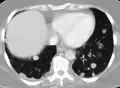

Initially, nearby lymph nodes are struck early.[9] The lungs, liver, brain, and bones are the most common metastasis locations from solid tumors.[9]

- Lung metastasis: cough, hemoptysis and dyspnea[9] (shortness of breath)

Metastatic tumors are very common in the late stages of cancer. The spread of metastasis may occur via the blood or the lymphatics or through both routes. The most common sites of metastases are the lungs, liver, brain, and the bones.[10]